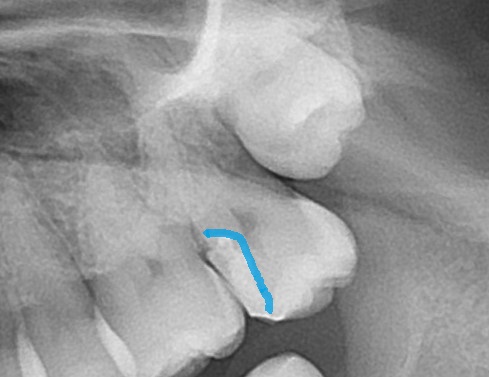

エックス線(レントゲン検査)で歯の中を見てみましょう。

一番奥に生えてきていない親知らずがあります。一つ手前の白く詰め物がされている歯です。

☝青い箇所がレジンが詰めてあります。

神経に近く、ほぼ神経に触れるように詰め物がされています。

☝詰め物がうまく詰められておらず、飛び出て段差になっていることも見て取れます。